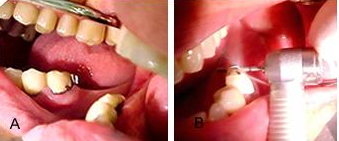

Figura 1A. Esta é a região onde serão realizados os implantes.

Figura 1B, com o alta rotação e uma broca diamantada foi removido o macho de encaixe do attachement, para a colocação dos implantes de das coroas imediatas na posição correta.

Figura 3 a e b.

No primeira figura vemos o guia cirúrgico no modelo e segunda vemos o guia na boca do paciente, em posição para ser marcado o local da perfuração a ser realizada no osso. Deve-se fazer a perfuração, o mais próximo do local marcado, se não possível, o cirurgião deve optar por uma posição que aproveite ao máximo a estrutura óssea, evitando situações que criem dificuldades, ao protesista, no momento de se colocar as coroas.